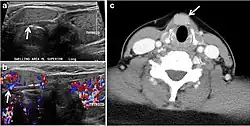

Fig. 13. A 27-year-old female patient known to have goiter. a, b Axial and sagittal enhanced CT scan images of the neck demonstrate a heterogeneously enhancing, enlarged thyroid gland with scattered calcifications (white arrow), cystic changes, and substantial retro-sternal extension (black asterisks). No lymphadenopathy or substantial airway narrowing.[1]

Fig. 14. A 19-year-old male patient known to have multi-nodular goiter and FNA, showing underlying Hashimoto's thyroiditis. a, b Sagittal and transverse greyscale and colour Doppler ultrasound of the neck demonstrate a hypoechoic enlarged right thyroid lobe with small hyperechoic regenerative nodules and marked hypervascularity (white arrows). c, d Enhanced axial CT scan images of the neck demonstrate a heterogeneously enhancing and enlarged thyroid gland, left more than right lobe, and the trachea is markedly narrowed.[1]

Fig. 15. A 33-year-old female patient who presented with neck swelling and pain and was later diagnosed with Hashimoto's thyroiditis. an Axial enhanced CT scan of the neck demonstrates minimal diffuse enlargement of the thyroid gland, especially the isthmus (white arrow). b Transverse greyscale ultrasound of the neck demonstrates heterogeneously enlarged thyroid and thickened isthmus, measuring 8.6 mm.[1]